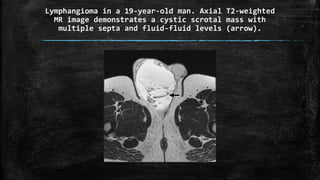

Lymphangioma in a 19-year-old man. Axial T2-weighted

MR image demonstrates a cystic scrotal mass with

multiple septa and fluid-fluid levels (arrow).